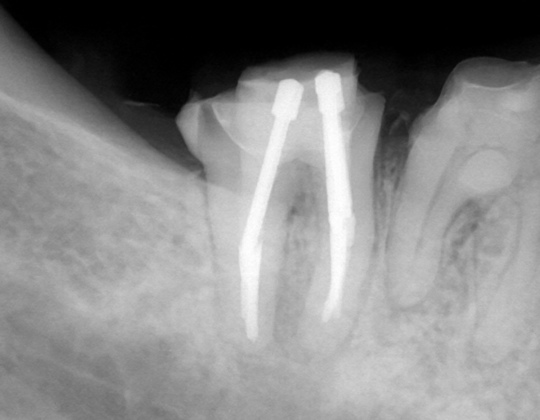

自費根管治療症例7 治療前(感染根管処置、穿孔封鎖)

「銀歯がひどく痛む」

前医の治療の時に根管に孔が空いたようです

管の途中に孔が確認できます

銀歯です

精密根管治療(自費根管治療)治療開始

精密根管治療(自費根管治療)、治療回数3回、治療期間約1週間、治療費(大臼歯再治療)15万3千円+4,500円X2回 ジルコニアクラウン6万9千円

レントゲン写真

孔はMTAセメントで封鎖しました

根管充填もMTAセメントによる穿孔封鎖もうまくいきました

根の周りの黒い影がなくなり、骨もほとんど回復して、痛みもありません